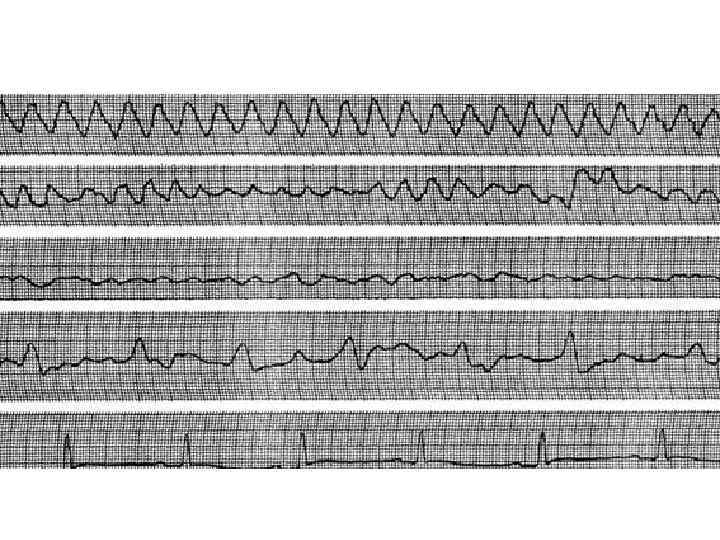

Трепетание и мерцание желудочков Трепетание желудочков — частое (до 200– 300 в мин) ритмичное их возбуждение, обусловленное устойчивым круговым движением импульса (re-entry), локализованного в желудочках. Трепетание, как правило, переходит в мерцание желудочков. Мерцание (фибрилляция)желудочков – столь же частое (до 200– 500 в мин), но беспорядочное, нерегулярное возбуждение и сокращение отдельных мышечных волокон желудочков. ЭКГ-признаки: – при трепетании желудочков на ЭКГ частые (до 200– 300 в мин) регулярные и одинаковые по форме и амплитуде волны трепетания, напоминающие синусоидную кривую; – при мерцании (фибрилляции) желудочков на ЭКГ регистрируются частые (до 200– 500 в мин), но нерегулярные волны, отличающиеся друг от друга различной формой и амплитудой.

Эпизод трепетания желудочков